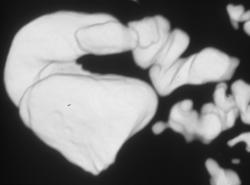

Virtual Imaging of the Cecum and Appendix